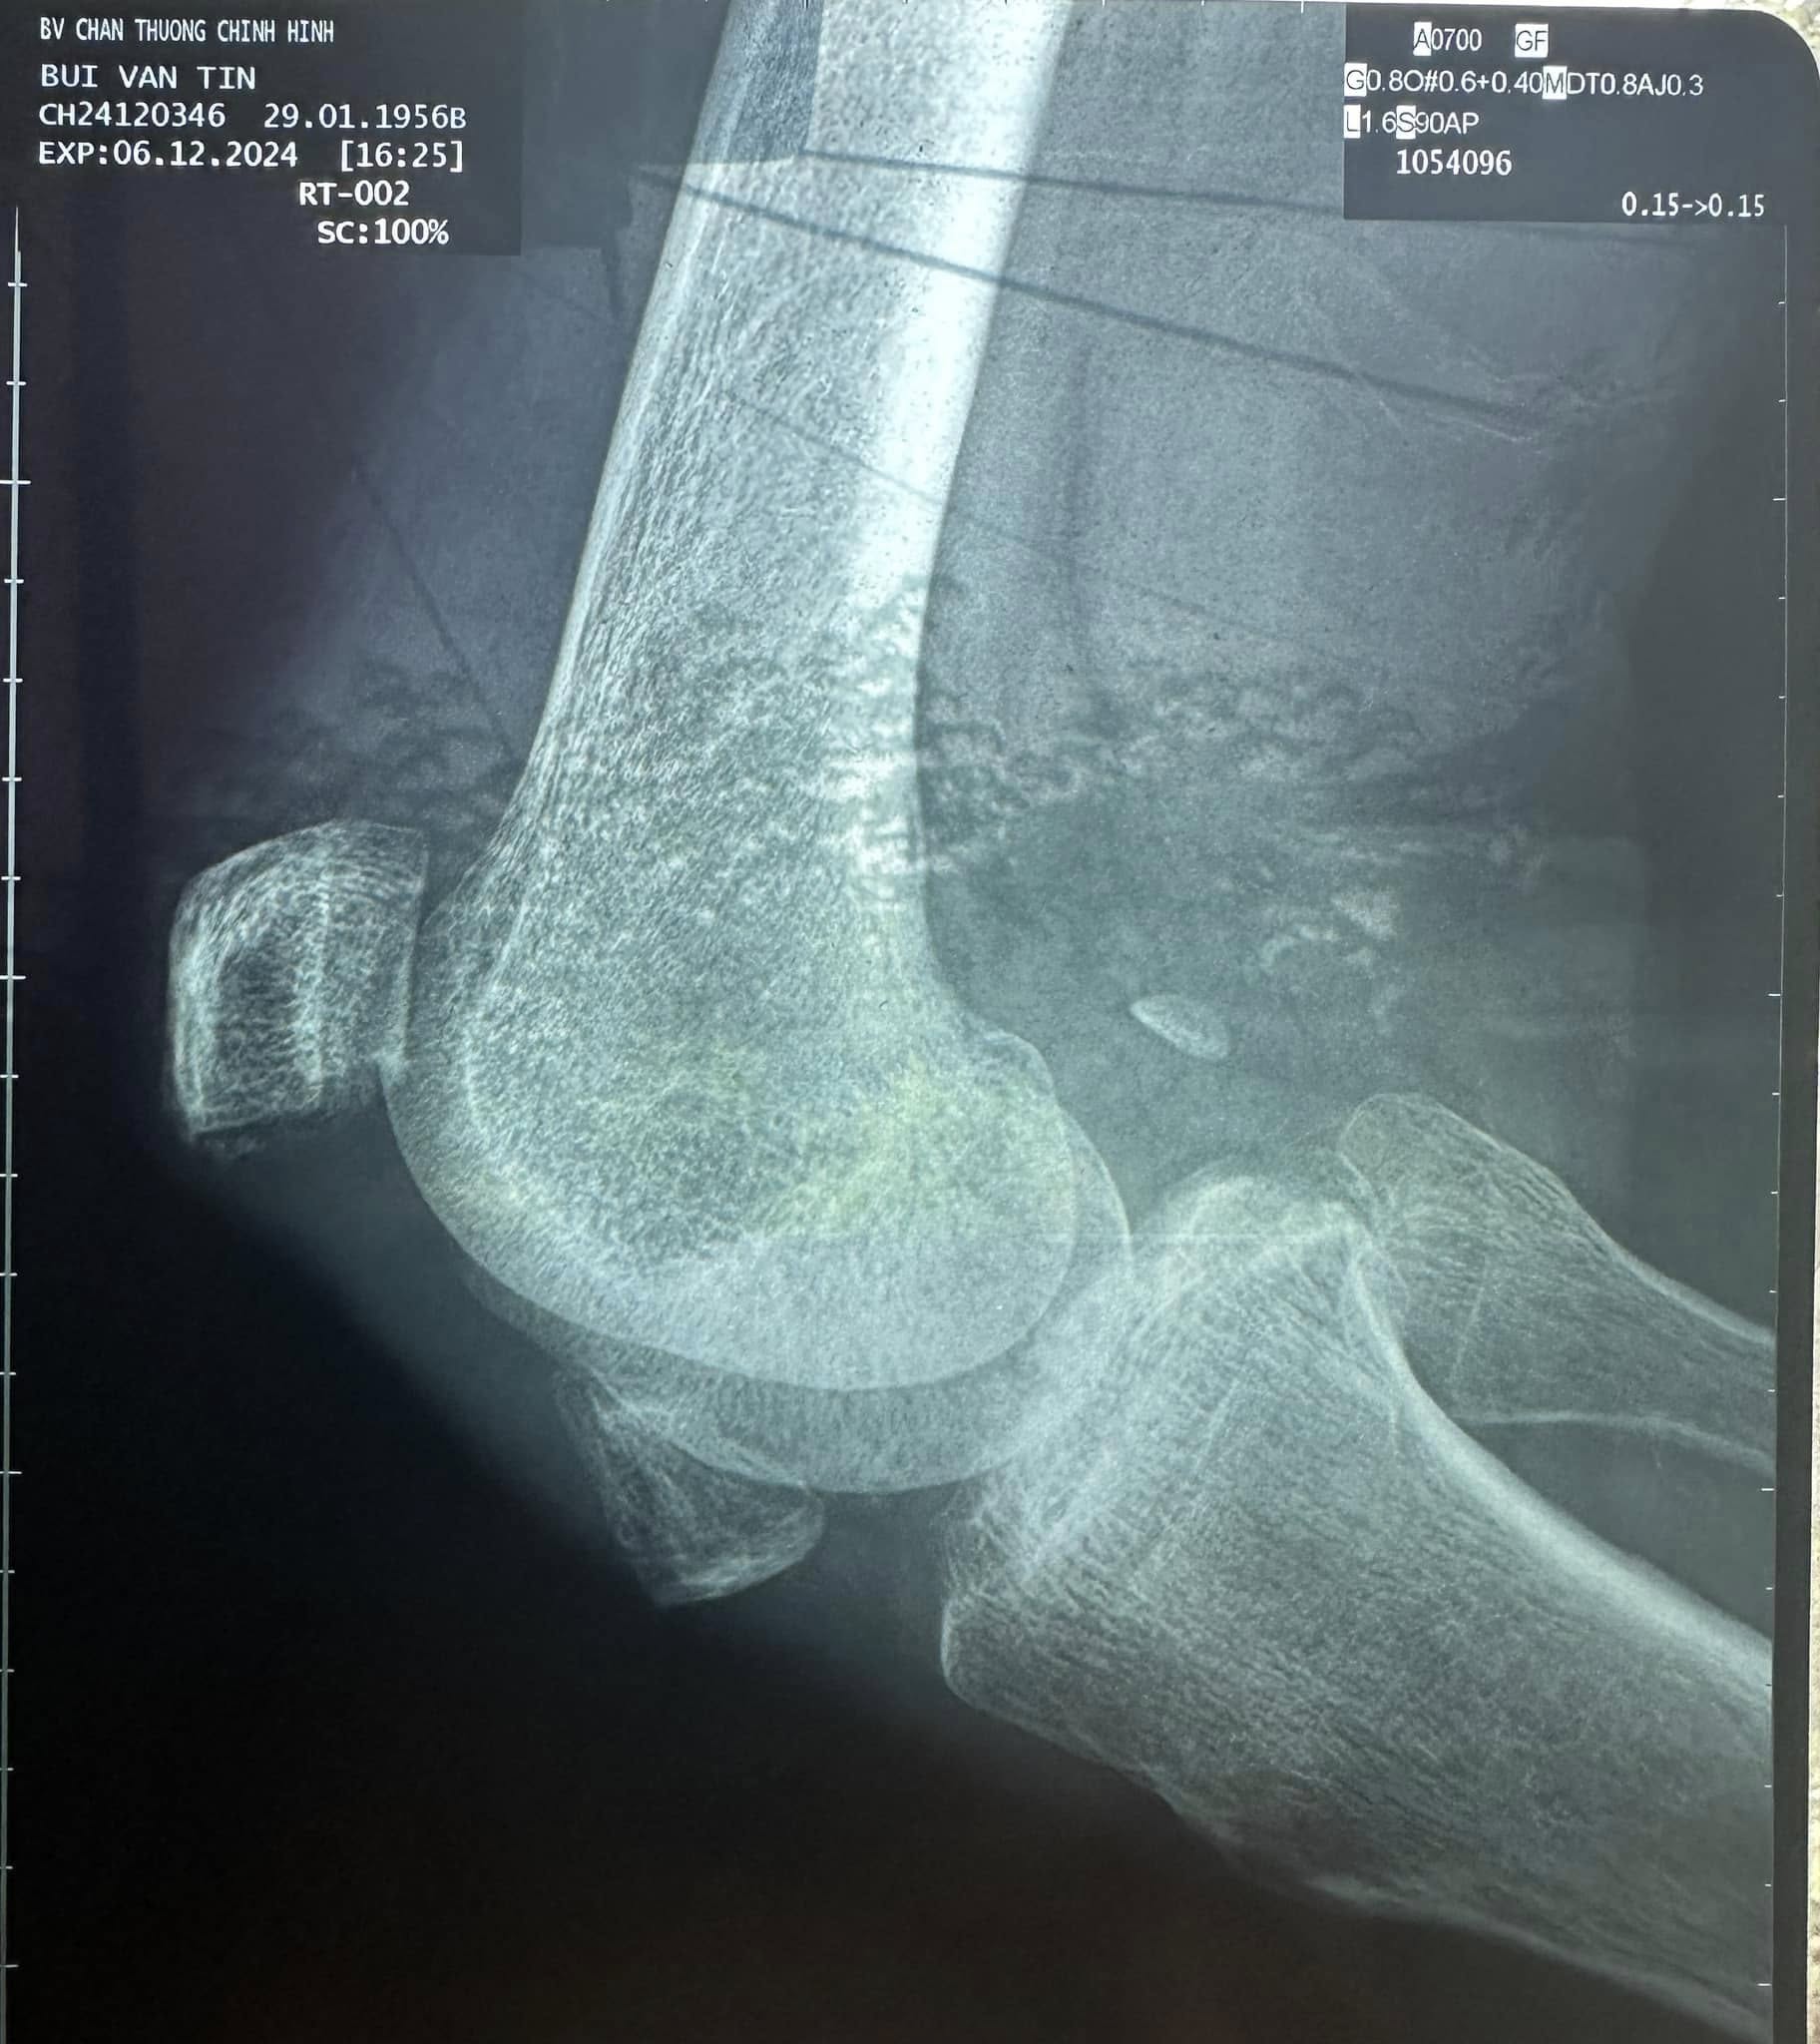

Mới đây, nhạc sĩ Tô Hiếu tiếp tục cập nhật thông tin, hình ảnh về sức khỏe của Thương Tín. Được biết, chiều ngày 6/12, nam nhạc sĩ cùng gia đình Thương Tín đưa nam diễn viên đến bệnh viện chấn thương chỉnh hình TPHCM để khám bệnh.

Anh thông báo: “Chân phải của Thương Tín bị bể đôi bánh chè khớp gối, bác sĩ nói không thể hồi phục lại được nữa. Chân trái, khớp đầu gối bị viêm khớp nặng, uống thuốc điều trị lâu dài.

Bác sĩ nói, sức khoẻ Thương Tín hiện tại rất yếu, khi nào sức khoẻ tốt mới mổ lấy 2 miếng bánh chè ra được”. Bác sĩ cũng lưu ý nam diễn viên 6x nên di chuyển bằng xe lăn.

Chia sẻ thêm với phóng viên, nhạc sĩ Tô Hiếu cho hay, bệnh của Thương Tín là do vụ tai nạn xe ở Phan Rang vài tháng trước. Thời điểm đó, Thương Tín cũng được mọi người đưa vào bệnh viện nhưng không phát hiện ra tình trạng trên.

Gia đình sau đó đón về. Tới thời điểm hiện tại, do sức khỏe yếu, việc đi lại quá khó khăn và đau đớn nên gia đình đưa nam diễn viên lên Sài Gòn thăm khám. Được biết, chi phí thăm khám bệnh cho Thương Tín chiều qua được nhạc sĩ Tô Hiếu chi trả hoàn toàn.